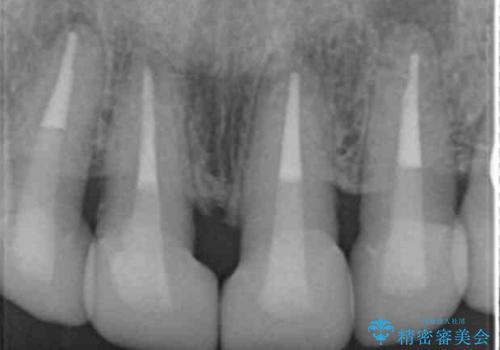

4年半前のクラウン装着時と変わらず、まるで天然歯のように自然に見えました。

患者様の良好なセルフケアと精密な適合の良いクラウンにより、歯肉の腫脹や退縮も認められませんでした。

4年半前に行った治療に大変ご満足頂き、他の部位の治療のため再来院して下さいました。